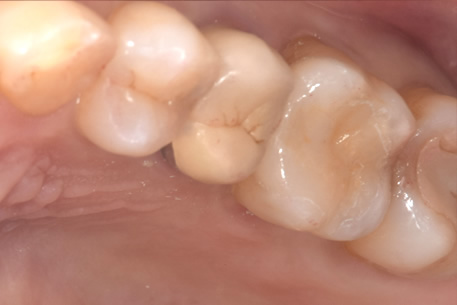

症例① セラミックインレー

治療後

治療方針 つめ物がすでに入っている歯です。そのため、見た目では虫歯があるかどうかわかりませんでしたので、レントゲンを撮影しました。すると、つめ物の中で虫歯になっていることがわかりました。虫歯は、とても大きくなっており神経に近い部分まで進行していました。

治療内容 神経が保存できるかどうか経過をみるために、覆罩といって、神経を守るための処置を行いました。2ヶ月ほど経過を見て、症状が出ないことを確認して、つめ物の型をとり、つめ物をいれていきました。

治療期間 3ヶ月

リスク・副作用 治療後に冷たいものがしみるなどの症状がでることがあります。つめ物を入れた後に痛みなどの症状が出てしまう場合は神経を取り除く治療が必要になります。

費用 ・セラミックインレー:55,000円(税込)

経過観察中に症状がでなかったため、セラミックのつめ物をいれていった。